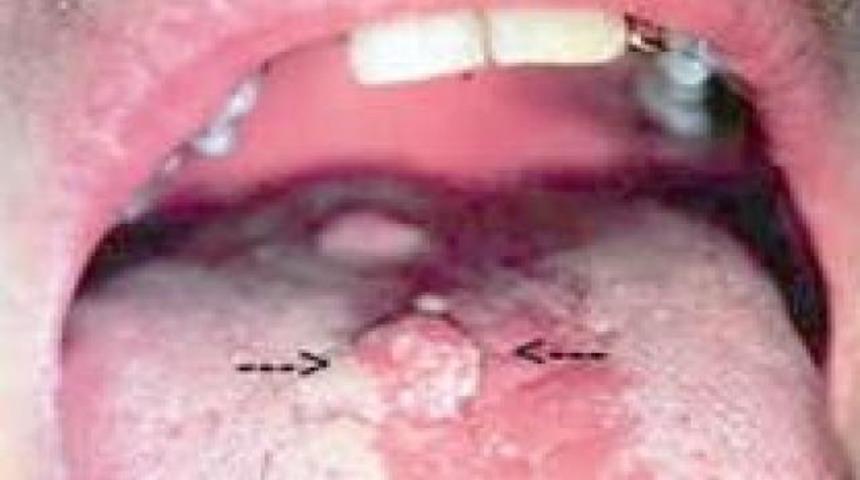

HPV virusunun 130 dan fazla tipi mevcuttur.Özellikle HPV 16 kanser vakalarında görülen tipdir. Bu virus oral seks yolu ile bulaşabilmektedir.Ağız mukoza yapısı genital bölge mukozası ile benzer yapıda olup bu virusun yerleşmesine ve siğile benzer lezyonlar oluşmasına neden olur.Yapılan karşılaştırmalı grup çalışmalarında oral seks yapan ve HPV virusu olan hastalarda kanser vakaları 3 kat fazla görülmüştür. Sigara ve alkol kullanımı bu oranı daha da arttırmaktadır.

Özellikle bekareti önemli olduğu toplumlarda oral seks sıklıkla yapılmaktadır.Bu yolla bulaşan HPV virüsünü meme başı görünümünde siğillere sebep olmaktadır.Bu dokular bazı etkenler de eklendiğinde ağız kanserine dönüşebilir.Ağız kanserlerinin tüm kanserler içinde görülme sıklığı %2-5 oranındadır.

HPV'nin en sık neden olduğu belirti genital bölgede görülen siğillerdir. Ciltten hafif kabarık, yumuşak olan bu siğiler cinsel bölgeyi oluşturan deride, vajina ile makat arasında, anüs etrafında, bacakların iç kısmında, penis ucunda ya da çevresinde görülebilir. Anal ya da oral seks sonrasında ağız içi ve makat içinde de siğiller ortaya çıkabilir. Bazı durumlarda vajina içinde ve rahim ağzı üzerinde de siğiller olabilir.